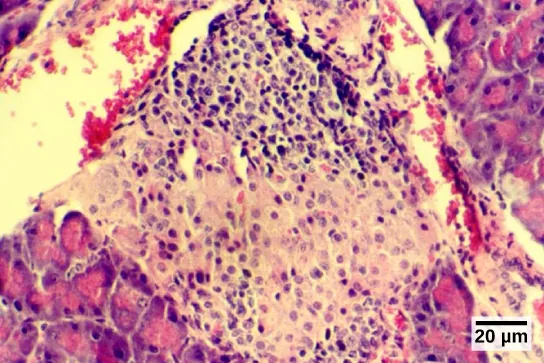

The endocrine cells of the pancreas form clusters called pancreatic islets or the islets of Langerhans, as visible in the micrograph shown in Figure 37.20. The pancreatic islets contain two primary cell types: alpha cells, which produce the hormone glucagon, and beta cells, which produce the hormone insulin. These hormones regulate blood glucose levels. As blood glucose levels decline, alpha cells release glucagon to raise the blood glucose levels by increasing rates of glycogen breakdown and glucose release by the liver. When blood glucose levels rise, such as after a meal, beta cells release insulin to lower blood glucose levels by increasing the rate of glucose uptake in most body cells, and by increasing glycogen synthesis in skeletal muscles and the liver. Together, glucagon and insulin regulate blood glucose levels.

Micrograph shows purple-stained cells in a white tissue. The white tissue is surrounded by tissue that stains pink.

Figure 37.20 The islets of Langerhans are clusters of endocrine cells found in the pancreas; they stain lighter than surrounding cells. (credit: modification of work by Muhammad T. Tabiin, Christopher P. White, Grant Morahan, and Bernard E. Tuch; scale-bar data from Matt Russell)